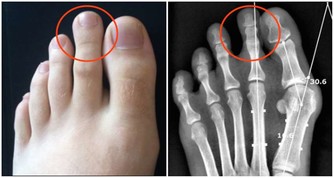

引起手麻較為常見原因的有以下幾種: 上肢神經卡壓:

一是拇、食、中指的麻木疼痛,

常有夜間麻醒史,醒後活動可好轉。

嚴重者可伴有手部肌肉萎 縮,影響手的精細動作,

這是因為正中神經在腕部受到壓迫,

即所謂的「腕管綜合徵」;

確診頸椎病並不困難,只要照一張X光片就可以了。